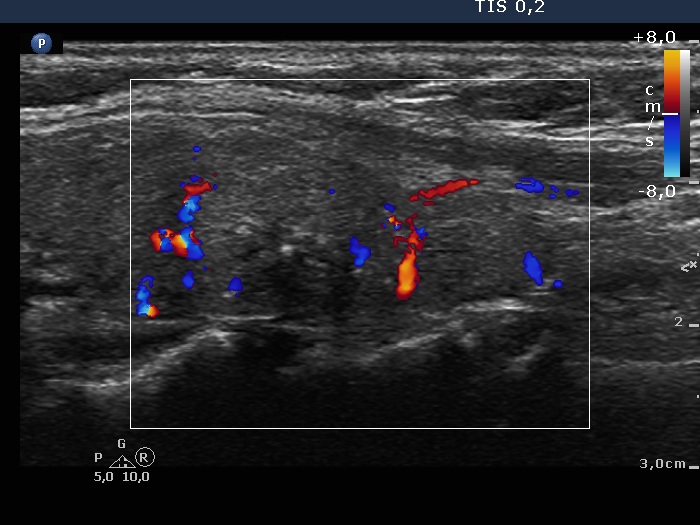

Left lobe, longitudinal scan, color Doppler mode. The vascularity is irregular.